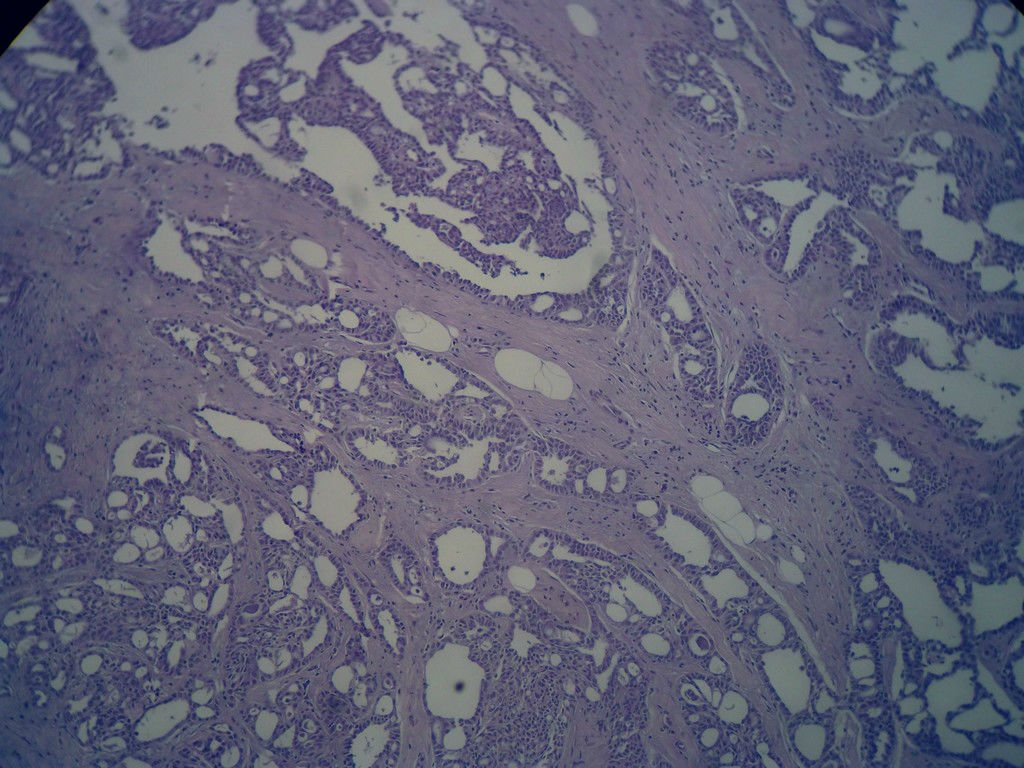

今天的一例术中冰冻。女,49岁,乳腺肿块。人气不旺,换个标题

腺病?癌?其他?(12楼常规,24楼免疫组化及会诊结果)图1

标签:浸润性导管癌 分泌癌 硬化性腺病

乳腺分泌型癌

冰冻符合乳腺腺病

占楼传常规1-11为冰对。

后取的恶性特征明显多了,神经内分泌癌?

浸润性导管癌。冰冻切片的诊断是很困难,直接诊断癌风险很大,但是在明显正常的导管间这种成片、成巢有腔的细胞团块也不是良性的表现,有的还似乎有围绕正常导管生长的倾向。诊断ADH还可以,但是不能归到任何一种DCIS的生长方式里。这例值得我好好学习。